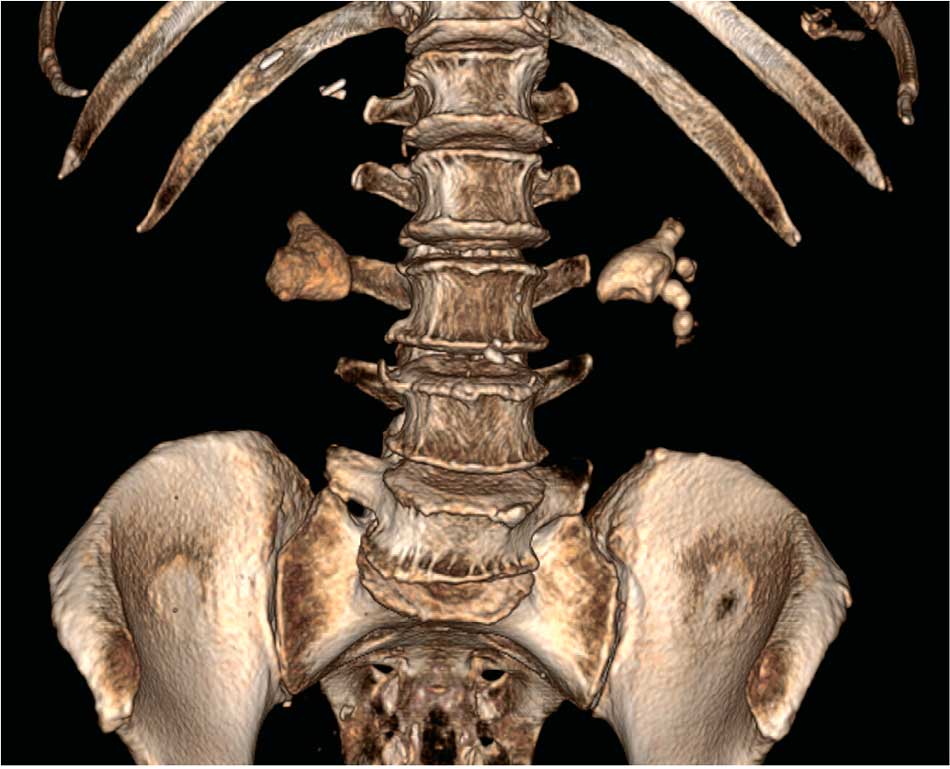

Пациентка И. 68 лет. Диагноз: Коралловидные камни обеих почек. Госпитализирована с жалобами на периодическое повышение температуры тела до фебрильных цифр. По данным КТ от 04.08.2021 г.: в чашечках и лоханке правой почки коралловидный камень (К2) размером 31х34 мм, плотностью 380 HU. В чашечках и лоханке правой почки коралловидный камень (К3) размером 32х28 мм, плотностью 450 HU. Двусторонняя пиелокаликоэктазия (рис. 6).

Рис. 6. Пациентка И. КТ почек от 04.08.2021,3D-модель, фронтальная проекция: до операции

Учитывая наличие лихорадки и двусторонней пиелоэктазии, первым этапом лечения пациентке выполнена двусторонняя нефростомия. Через 2 недели антибактериальной терапии, назначенной с учетом результатов посева мочи, полученной при пункции чашечно-лоханочной системы почек при установке нефростом, выполнены ПНЛТ справа и стентирование левого мочеточника. В послеоперационном периоде нефростомические дренажи с обеих сторон были удалены (рис. 7).

Рис. 7. Пациентка И. КТ почек: состояние после ПНЛТ справа и стентирования левого мочеточника